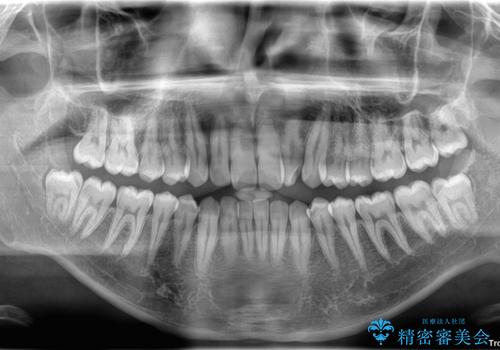

- 「上下の前歯がガタガタしているのが気になる」とのことで来院された患者様です。

上下顎前歯部に叢生(歯の重なり・ガタつき)を認め、見た目だけでなく、歯磨きのしにくさも気にされて来院されました。

そのため今回は、プラスチックブラケット+メタルワイヤーによるクリアブラケットによる治療を選択しました。